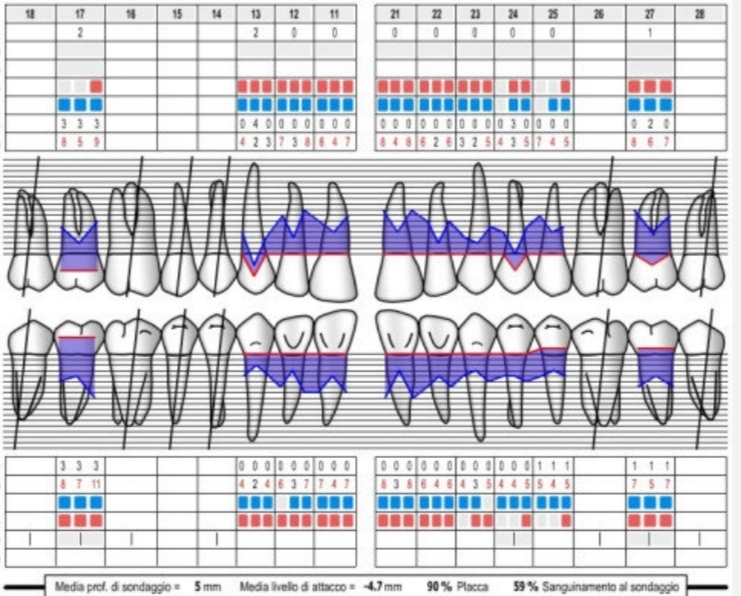

Badanie CPITN to przesiewowe bezbolesne i szybkie badanie wykonywane w czasie kompleksowego badania stomatologicznego

Dotykanie sondą periodontologiczną okolicy przyzębia pozwala ocenić:

- krawawienie dziąseł

- obecność płytki nazębnej

- obecność kamienia nazębnego

- obecność kieszonek przyzębnych oraz ich głębokość

- kieszonki dziąsłowe > 3,5 mm świadczą o chorobie przyzębia

- Higienistka przeprowadza instruktaż higieny, wybarwienie płytki nazębnej i wstępną higienizację, a w przypadku zapalenia przyzębia status periodontologiczny pozwalający monitorować przebieg choroby i postępy w leczeniu